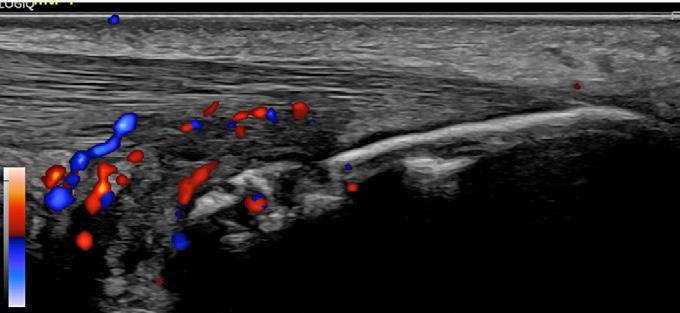

Figura 1. Entezită activă definită OMERACT la un pacient cu artrită psoriazică. Examinare în secțiune longitudinală, în scară gri și Power Doppler, a inserției tendonului Ahile. Se decelează o zonă hipoecogenă cu ștergerea aspectului fibrilar, eroziune la nivelul calcaneului cu semnal Doppler în interior. Se evidențiază și bursită retrocalcaneană cu activitate Doppler; aparat GE LOGIQ E10, sondă liniară de 4-20 MHz.